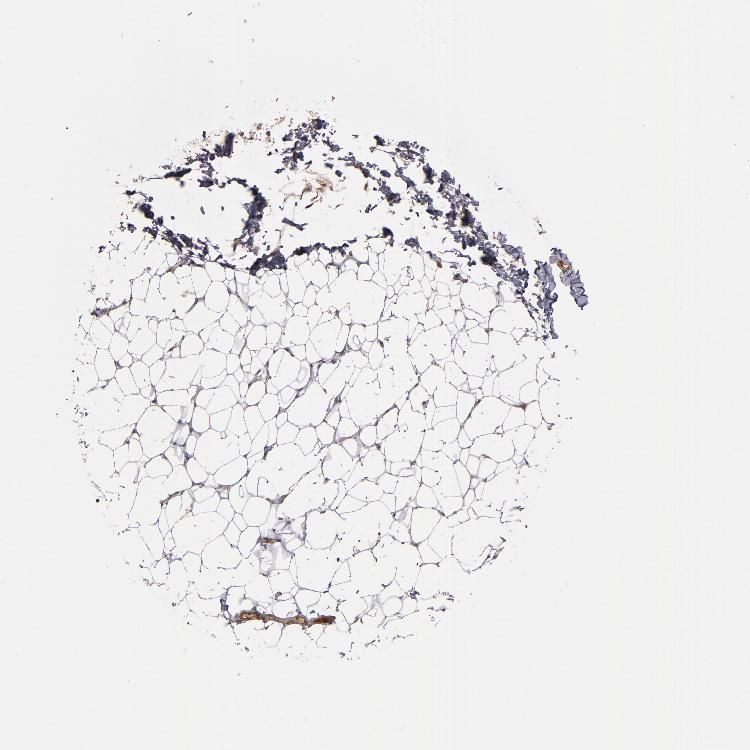

SOFT TISSUE 1 - Antibody stainingi

Antibody staining in the annotated cell types in the current human tissue is reported as not detected, low, medium, or high, based on conventional immunohistochemistry profiling in selected tissues. This score is based on the combination of the staining intensity and fraction of stained cells.

Each image is clickable and will lead to virtual microscopy that enables deeper exploration of all samples and also displays staining intensity scores, fraction scores and subcellular localization as well as patient and tissue information for each sample.

Antibody HPA002803

Fibroblasts Low